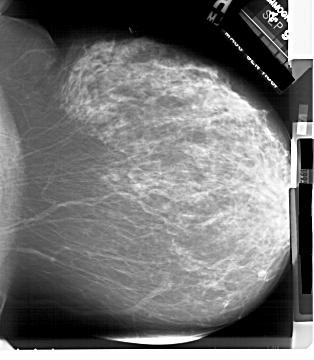

A_1899_1.RIGHT_CC

RIGHT_CC LINES 6106 PIXELS_PER_LINE 5326 BITS_PER_PIXEL 12 RESOLUTION 43.5 NON_OVERLAY